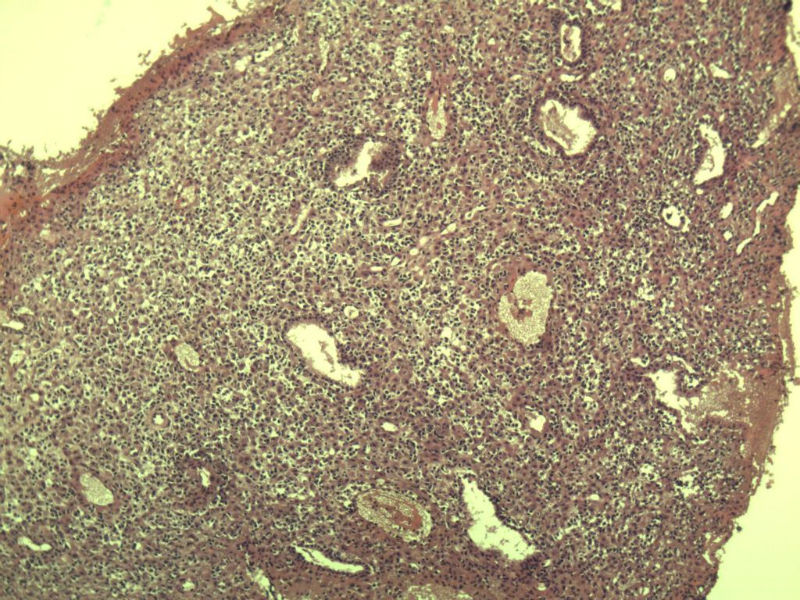

这是另外一个 40岁 经期延长 流血量增多 半年 这是蜕膜样变吧 有什么意义吗? 要报告不?